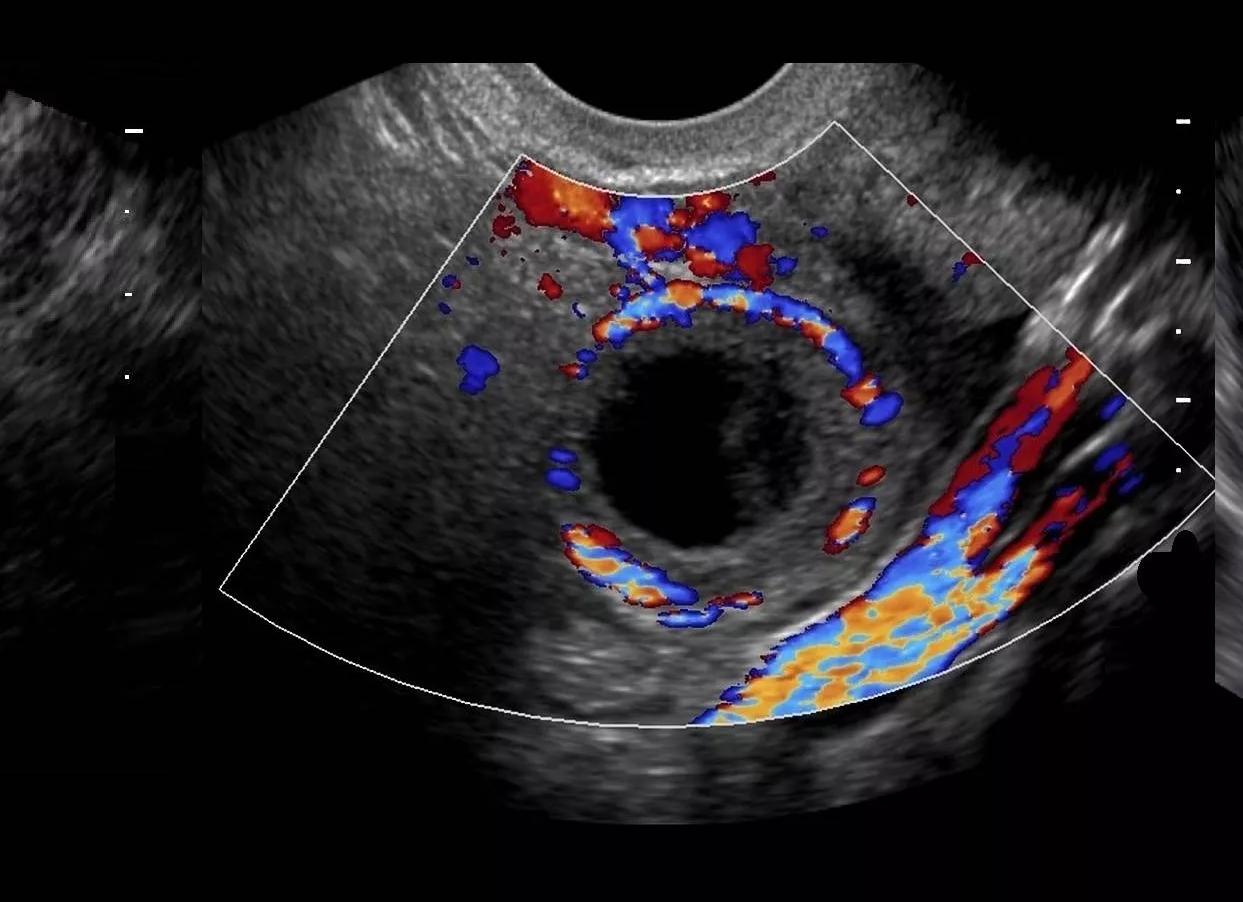

Лютеиновая железа (желтое тело) — динамический орган, который меняется в зависимости от фазы менструального цикла. Она начинает активно расти после наступления овуляции и полностью инволюционирует, если беременность не наступила. Лютеиновая железа функционирует в период репродуктивного возраста. При трансвагинальном исследовании в течение 3-8 дней она определяется в области одного яичника и представляет собой небольшой мешочек с неровными краями и различной эхогенности. Как было сказано ранее, она определяется после наступления овуляции и во время беременности до 7-8 недель.

Желтое тело на УЗИ выглядит как неоднородный мешочек в области яичника. В зависимости от его размеров врач может сделать вывод о наступившей беременности или о появлении патологий в репродуктивных органах.

Лютеиновая железа визуализируется на мониторе ультразвукового сканера в виде округлого мешочка в яичнике, который имеет неоднородную структуру. Если его не видно:

Когда и как обнаруживается желтое тело на УЗИ? Появление желтого тела происходит во второй половине менструального цикла – это норма. Процесс запускается после того, как до конца развитый фолликул лопается, а из него в организм поступает сформированная и созревшая для оплодотворения яйцеклетка. Эта важная железа отвечает за сохранность и функционирование яйцеклетки до того момента, когда она переместится из брюшной полости в маточную трубу для оплодотворения. Именно в этот момент на УЗИ можно определить наличие этой железы. УЗИ четко показывает, как выглядит эта железа и где она расположена. Это небольшой мягкий мешочек, который расположен возле одного из яичников. Если цикл менструации не имеет сбоев, то железа образуется практически в одно и то же время. Если на УЗИ видно ее отсутствие, то можно говорить о наличии заболеваний или патологий в эндокринной или репродуктивной системе. Если цикл не стабилен, то отсутствие желтого тела может являться следствием простой задержки в наступлении месячных.